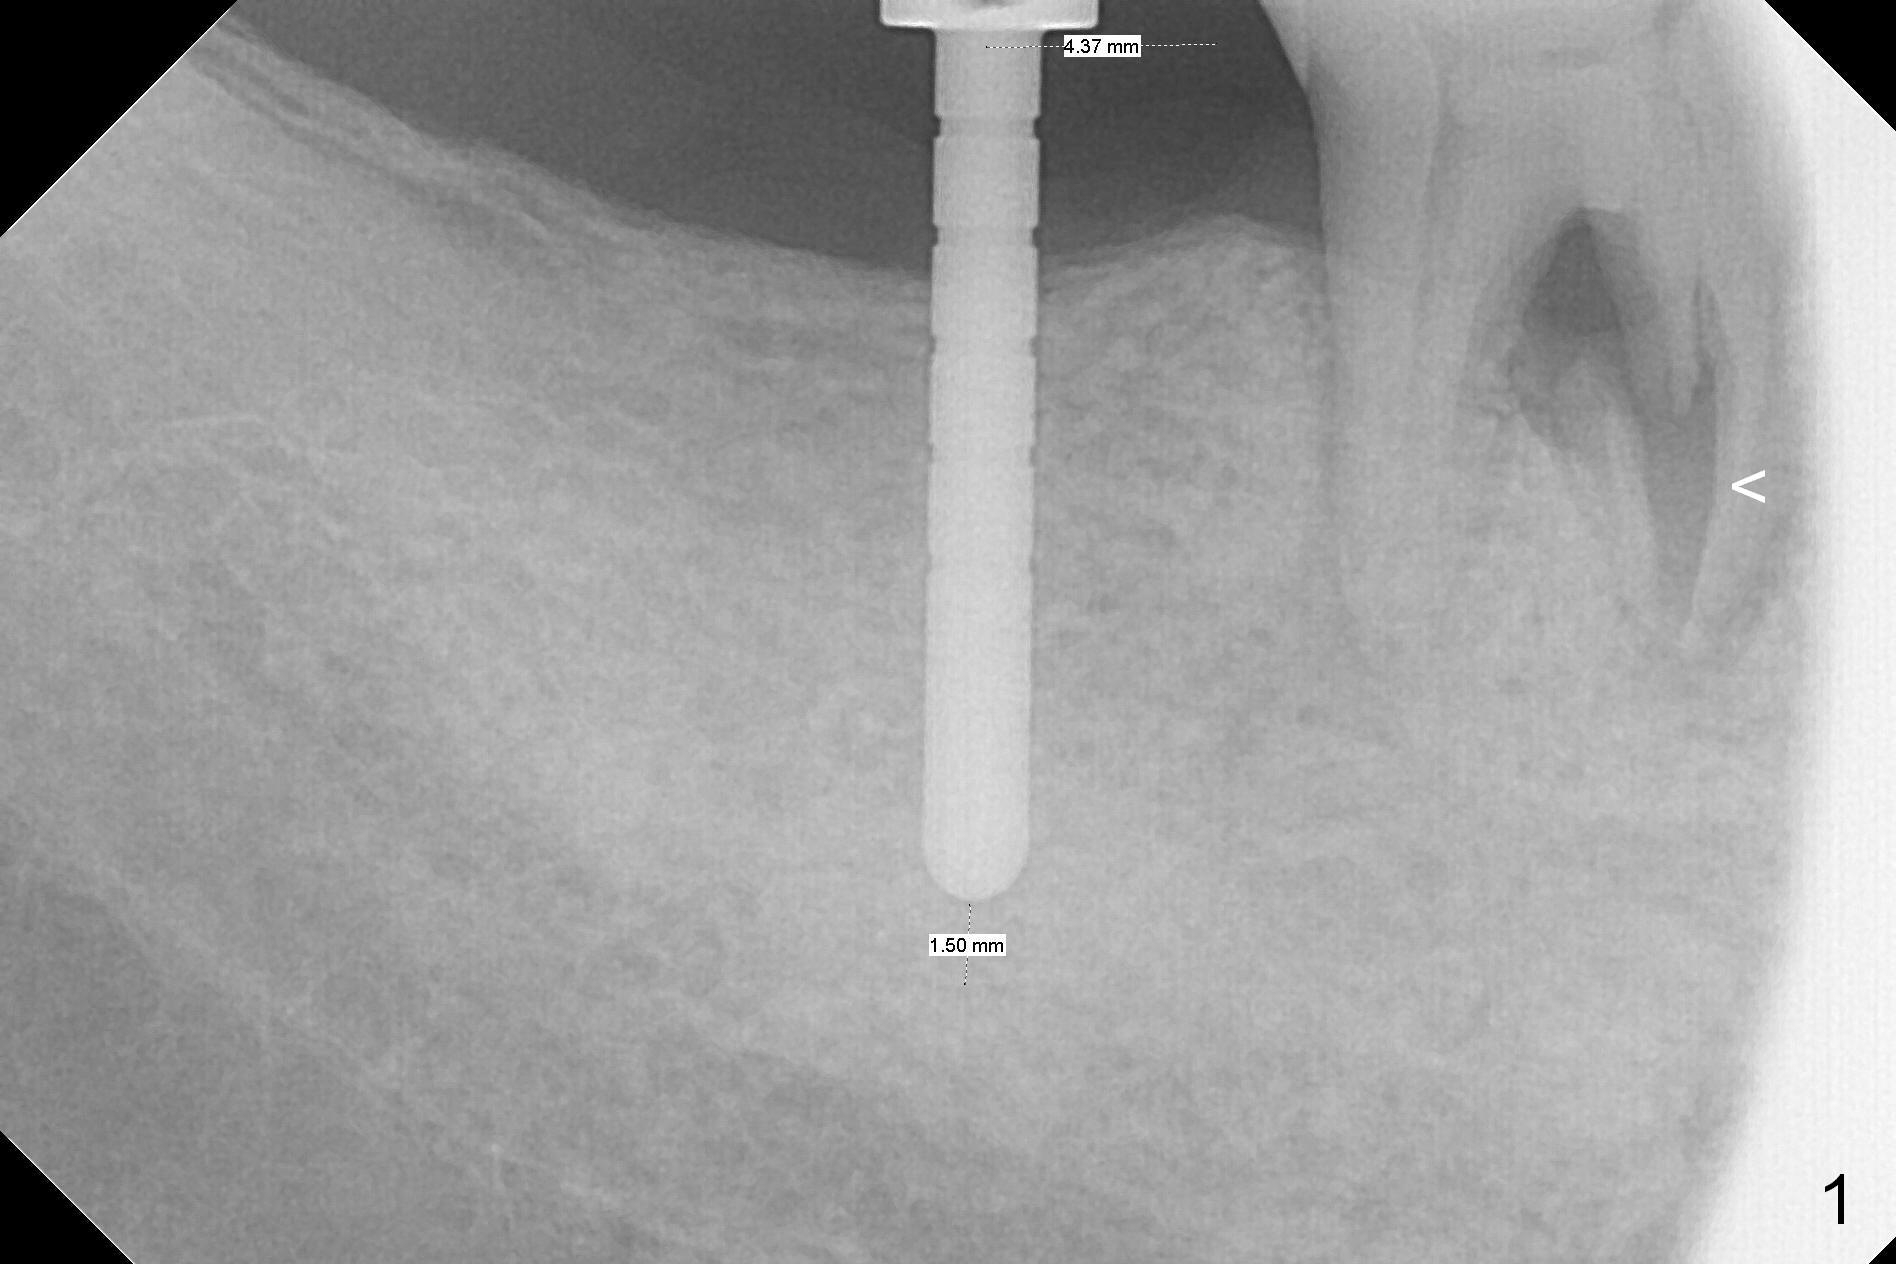

The leukoplakia at the sites of #31 and 32 is most likely related to smoking and the supraerupted teeth #1 and 2 (Fig.0 ^). After osteotomy for 11.5 mm at #31 (Fig.1), it appears that the bone height is not as much as expected. The last two drills for sequential osteotomy are 4.3x13 and 4.8x11.5 mm. A 5x11.5 mm UF implant is placed slightly subcrestal with insertion torque > 50 Ncm (Fig.2). Following placement of 6.5x2 mm healing abutment, the opposing tooth needs adjustment for height. Orthodontic intrusion of the opposing tooth is scheduled 2 days later. It is accidental to find root fracture of the mesial root of the tooth #30 (Fig.1 <). There is minimal bone resorption coronally 5 months postop (Fig.3). A provisional is fabricated at #31 to assist in intrusion of the tooth #2. A crown is cemented 11.5 months postop (Fig.4); the leukoplakia at #31 seems to lessen. The tooth #30 is lost during the pandemic, followed by looseness of the crown and abutment at #31. When the complex is reseated, the occlusal scheme is changed, suggesting incomplete seat of the abutment earlier (Fig.5).